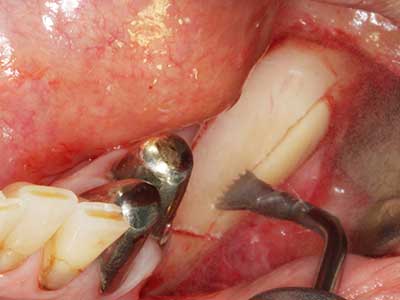

Piezo surgery has additional advantages when harvesting bone blocks. In addition to the high precision with osteotomy described above, the use of the thin saw tips specifically minimizes loss of material. Greater loss of material during harvesting can be expected with the thicker instrument tips, particularly when using Lindemann drills (Lakshmiganthan, Gokulanathan et al. 2012). The basal separation, which is necessary particularly for retromolar block transplants, is simplified by specially designed rectangular saws, with the result that piezo surgery is viewed as a precise, simple and safe procedure for harvesting retromolar bone blocks (Happe 2007) (Fig. 1-12).